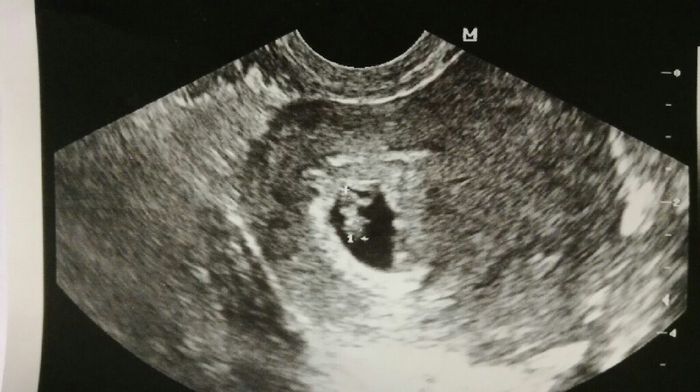

Prima ecografia

Da Paola , Il 3 Aprile 2017 alle 15:32

Oggi prima ecografia. Sono di 6 settimane e 5 giorni. Che bello si vedeva il battito.Il mio pupazzetto:)Che amore...